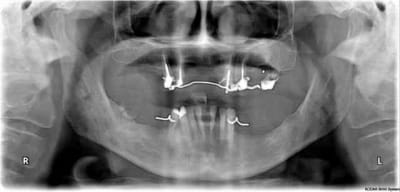

(je joins la pano et deux photos, je précise qu'en rétroalvéolaire, les racines antérieures et prémolaires en haut sont "bonnes" même si la dépose de magnifiques RCR compos infiltrés donne l'illusion du contraire)

HAIG, les racines en question ne présentent pas d'infection, pas d'obstacle au retraitement et une longueur suffisante pour espérer s'en servir.

Vous avez quoi avec le chiffre 4 ? j'ai 5 piliers en haut (15 13 23 24 25).